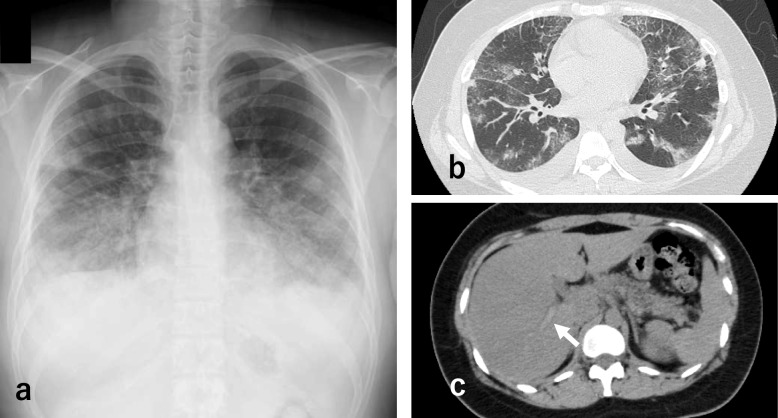

Case presentation: A 22-year-old woman presented with a persistent cough and was diagnosed with eosinophilic pneumonia and portal vein thrombosis. Although eosinophilic pneumonia improved with corticosteroid therapy, thrombotic complications worsened despite additional anticoagulant treatment. The administration of benralizumab led to marked improvement in thrombosis, resulting in clinical recovery.